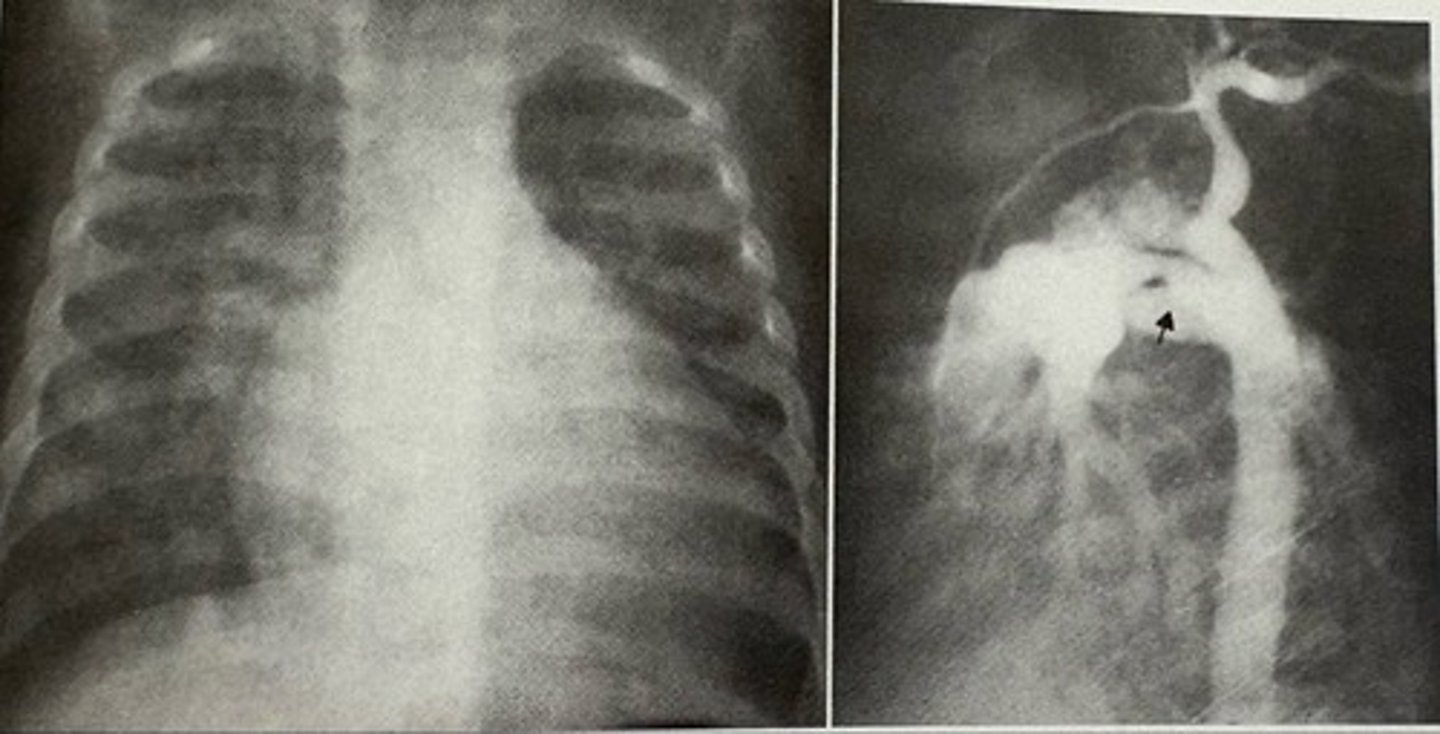

coarction of the aorta

what pathology is present?